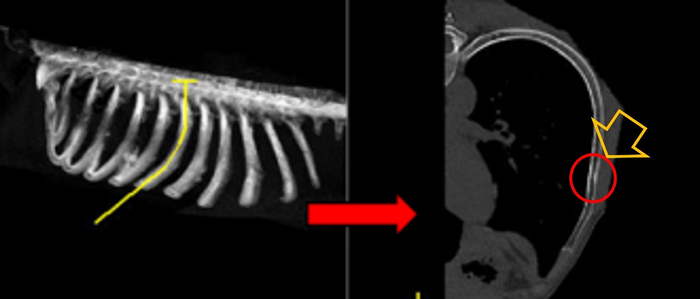

小知识2:CT可以更好地发现肋骨骨折,但是每个人双侧的肋骨有22-26根,单侧11-13根不等。而且肋骨的形态个体差异大,即使有经验的医生在诊断骨折时也需要非常地仔细。打个比方:诊断肋骨骨折就像翻阅一本500页的书,骨折的信息会隐藏在这500页中的任意一页,必须每一页都不漏。对于图4中的骨折,经验不足的医生很容易漏诊,往往这种漏诊就是王阿姨找不到痛的原因。

图4白色箭头所指处的弯曲骨折